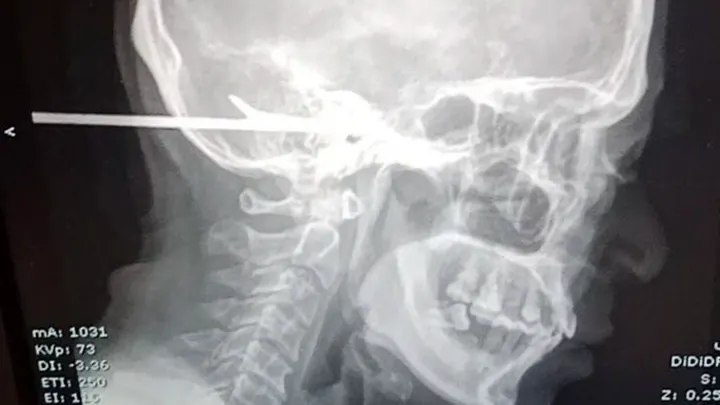

Ribar preživeo pogodak harpunom u glavu!

Lekari su ostali šokirani kada su otkrili da je ribar sa Tajlanda preživeo pogodak u glavu harpunom i to ne slučajno.! Sujit Klingtalay je sa prijateljima pecao i pio pivo u provinciji Nakhon Ratchasima na Tajlandu …

kada se 3 marta dogodio incident.

45-godišnjak je izjavio za medije da su se on i još jedan prijatelj posvađali oko toga koji je od njih svih upecao veću ribu. Iz besa, Klingtalajev prijatelj odlučio je da uperi harpun za pecanje u potiljak Klingtalajeve glave i ispali harpun koji se zaglavio unutar lobanje Klingtalajeva

Tamo su vatrogasci morali da odseku deo harpuna dugog stopala pre nego što su lekari mogli da izvrše operaciju. Sa samo nekoliko centimetara u Klingtalajevoj glavi od mesta gde je bio postavljen harpun, lekari u bolnici su uspeli da uklone harpun izveštava fox news

Ugao harpuna prošao je kroz l meso i u uho“, rekao je doktor Dok je drugi doktor izjavio da je Sudžit Klingtalej imao sreće što je živ.

Dodao je: „Da je harpun pogodio tj. udario malo dalje udesno, oštetio bi mu mozak i umro bi na licu mesta.“